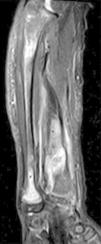

A la exploración física presentaba dolor y deformidad de dicho antebrazo. Se realizó radiografía simple, evidenciándose lesiones óseas displásicas en radio y cúbito derechos, así como una fractura patológica en el radio (fig. 1).